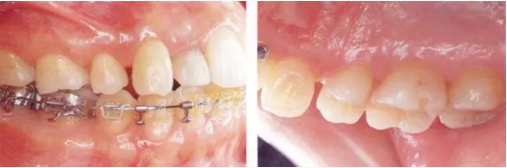

22222222222222222222222222222222222.png

▲圖19-5,6

▲圖19-5  初期治療完成后的狀態(tài),炎癥得到了很好的控制。

▲圖19-6  在下頜右側(cè)磨牙部植入種植體恢復(fù)垂直高度以及形成支抗點,開始正畸治療。